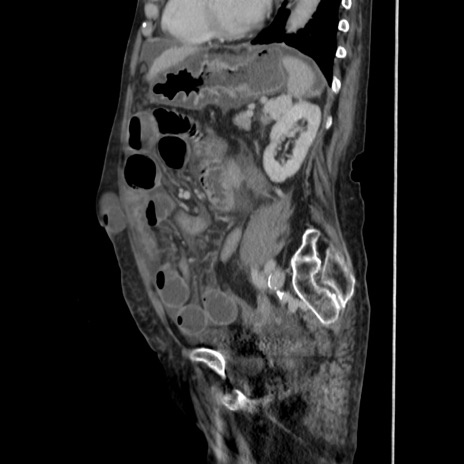

症例31(矢状断像)

【症例】80歳代 女性

【主訴】腹部膨満感

【現病歴】他院にて肝硬変にてフォロー中。1週間前から便秘、腹部膨満感、臍部腫瘤あり受診となる。

【既往歴】肝硬変

【身体所見】腹部膨隆あり、皮膚変化なし、疼痛なし。

【データ】WBC 4600、CRP 0.25